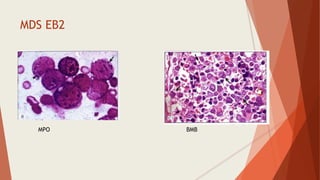

MDS EB2

MPO BMB